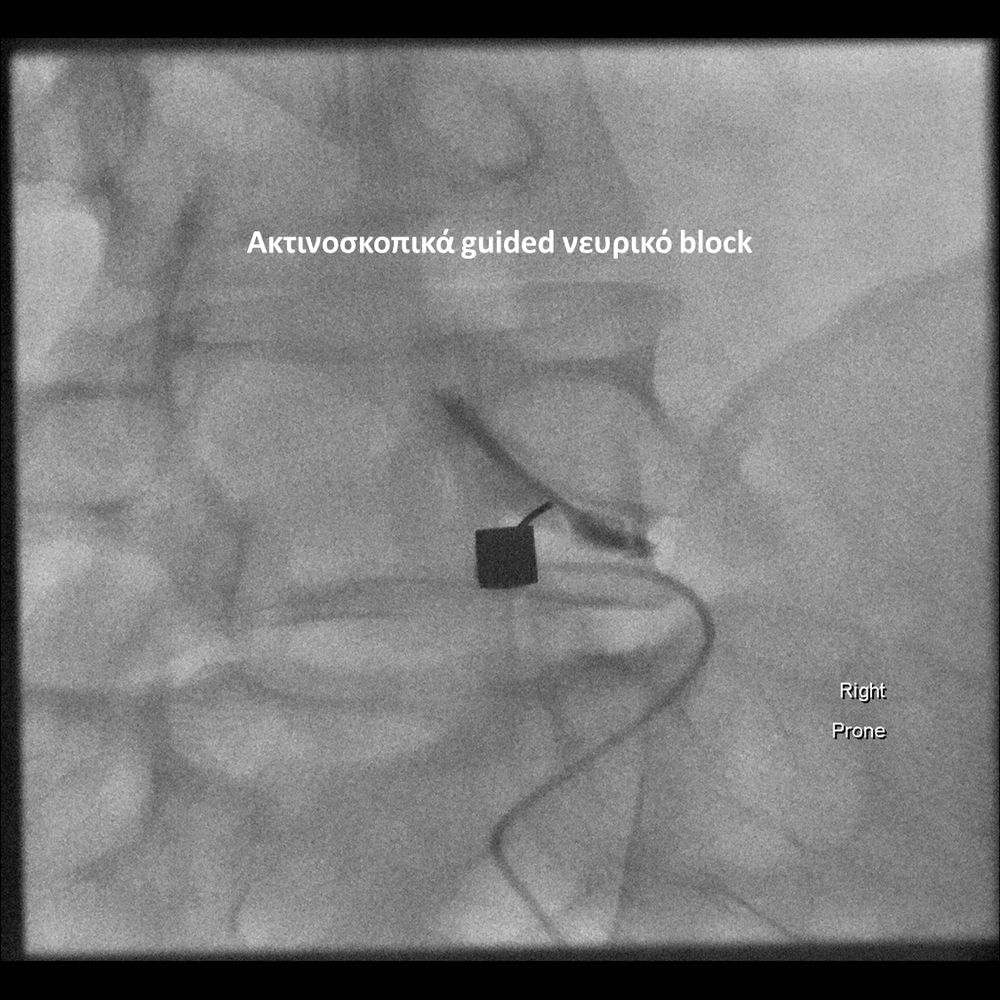

Με την βοήθεια της επεμβατικής ακτινολογίας είναι δυνατόν να πραγματοποιηθούν διαφορες ενέσιμες τεχνικές που αποσκοπούν στη μείωση του μυοσκελετικού πόνου, την ενίσχυση της αποτελεσματικότητας της φυσιοθεραπείας και την επιτάχυνση της διαδικασίας επούλωσης. Οι τεχνικές αυτές περιλαμβάνουν την κατευθυνόμενη έγχυση φαρμάκων ή πραγματοποίηση θεραπευτικών χειρισμών ακριβώς στη θέση τηςπαθολογία. Ετσι εξασφαλιζεται η μέγιστη αποτελεσματικότητα ( έως 95% κατά περίπτωση) και ασφάλεια σε σχέση με τυφλούς χειρισμούς χωρίς ακτινολογική καθοδήγηση.